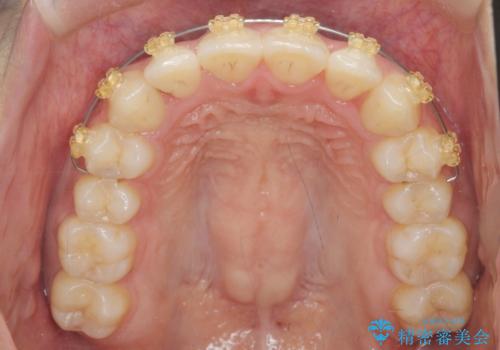

前歯のねじれ、すれ違いを改善 部分ワイヤー+マウスピース矯正

- インビザライン +部分ワイヤー矯正

- 上下前歯のすれ違い、ねじれのある歯並びの矯正治療を求めて来院されました。

上顎前歯のみの部分ワイヤー治療を約6ヶ月行い、ねじれの問題を解決したのち、マウスピース矯正で細かな歯列を整えていきます。